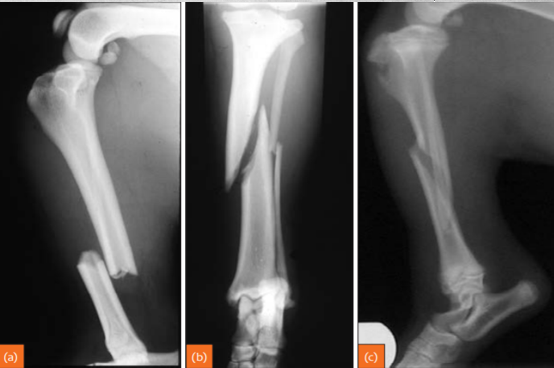

27

identify

classic osteosarcoma CCLR secondary to neoplasia metastasis to lungs first (other intestinal organs also poss.) osteosarc. can have both new bone formation as well as lysis.